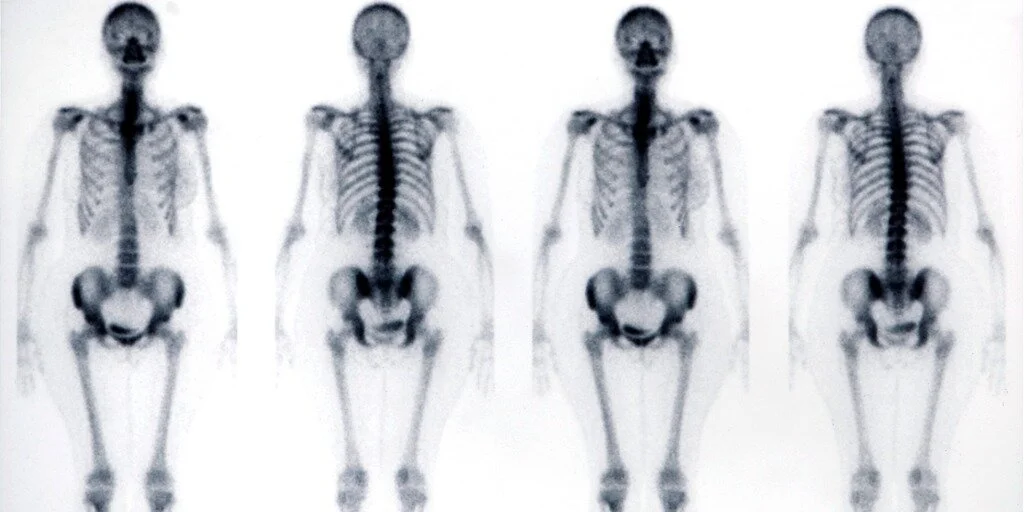

The radioactive material localises in specific parts of your body and is then detected by a gamma camera, creating an image of the area.

Normally there is a delay between the administration of the isotope and the scan that can range from several minutes to several hours. For example, the thyroid gland is scanned almost immediately after administration of the substance, whereas for a bone scan you will be asked to return approximately 3 hours after injection, during which time the radiopharmaceutical will have been taken up by the bones.